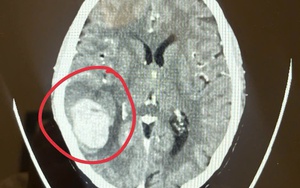

Phát hiện dấu hiệu lạ ở mặt khi đi chợ sớm, bệnh nhân làm ngay 1 việc khiến bác sĩ khen “quá sáng suốt”

Sống khỏe 2025-10-27T13:00:00Hành động này đã cứu bệnh nhân thoát khỏi mối nguy hiểm mang tên "đột quỵ".